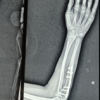

The patient was a 41-year-old male civil servant who was fit and well, had no regular medications, was non-diabetic, and was a non-smoker. He had no declared history of steroid use. The patient weighed 96 kg and was 5’11’’ tall, which gave him a body mass index of 29.6. The primary injury was sustained while playing football, he was tackled and fell onto a flexed left knee when he heard a “snap.” He was immediately unable to weight bear. He was initially taken to the hospital local to the football match where an X-ray was taken. The patient was then transferred to his local district general hospital. An ultrasound and an magnetic resonance imaging scan were performed, confirming the diagnosis of a patellar tendon rupture. The patient underwent a direct primary repair over a week after the initial injury. Postoperatively he was discharged in a brace and with oral Aspirin as venous thromboembolic chemoprophylaxis. He was reviewed in clinic 7 weeks postoperatively and his clinic note documents a “stumble following successful repair” which had led to a re-rupture. The patient underwent a revision direct repair 2 weeks later using an anchor suture, but no other biologic or non-biologic augmentation. Postoperatively, the knee was immobilized in a brace. One month after his revision surgery, the patient stumbled and fell again. He decided to attend a different hospital for a further opinion. Assessment at the next hospital confirmed a swollen leg with a stitch abscess in the distal aspect of the longitudinal wound (Fig. 1) and a palpable gap over the insertion of the patella tendon. The case was discussed with the plastic surgical team before proceeding with 2nd-time revision surgery.

The operation was performed with an orthoplastic approach with two orthopedic consultant surgeons and a plastic consultant surgeon present. The patient was positioned supine, and the whole right leg was prepped with chlorhexidine and betadine then a sterile, high thigh tourniquet was applied and inflated following elevation. The previous incision was extended proximally and distally. A massive gap was noted at the site of the patellar tendon insertion was a large hematoma. The wound washout was irrigated with 6 L of normal saline. The knee was further exposed, repeatedly irrigated and the end of the patellar tendon remnant was identified. The end of the patellar tendon was freshened and the distal pole of the patella was freshened with a burr. The previous suture anchor was removed. A new Arthrexã anchor sutures were inserted into the distal patella. A transverse 6 mm hole was drilled transversely across the patella and a 7 mm drill hole was through the tibial tuberosity. Semitendinosus tendon was harvested from the ipsilateral knee with the distal inserted left intact. The patellar tendon was directly repaired using the Arthrexã anchor sutures. The semitendinosus was fed through the patella and the tibial tuberosity drill holes secured with a 7 × 25 mm buried titanium interference (RCI) screw with the knee in extension. A cerclage wire was passed through a separate hole in the tibial tuberosity then it was fed superior to the patella through the quadriceps tendon creating a tension band construct. The surgical site was irrigated with pulse lavage. The tourniquet was deflated (tourniquet time: 56 min) followed by hemostasis with diathermy. The wound was closed with deeply interrupted 1 vicryl, 2.0 vicryl subdermal, and 3.0 monocryl to the skin. Postoperatively the patient had two further doses of intravenous teicoplanin and was prescribed prophylactic enoxaparin for 3 weeks. A check X-ray was done before discharge and a lightweight cylinder cast was applied before mobilizing toe touch weight-bearing. He was reviewed in the clinic at 2 weeks postoperatively. The knee was kept in full extension for 8 weeks with 4 weeks of enoxaparin venous thromboembolism prophylaxis and 4 weeks of 75 mg oral Aspirin. A clinical photograph is shown in Fig. 1. The patient was then allowed to sequentially increase his flexion in a range of movement brace by 30° every 2 weeks when not loading, going up to 0–90° by 6 weeks. When weight-bearing the patient wore his brace locked in full extension. At 6 weeks the patient then began flexing through a loaded knee. At 4 months postoperatively, the patient’s range of movement was 0–70° which had increased to 0–90° in 5 months. At 17 months postoperatively his active range of movement was 0–140, he had no pain, the wound had fully healed and he had returned to all activities, including football.